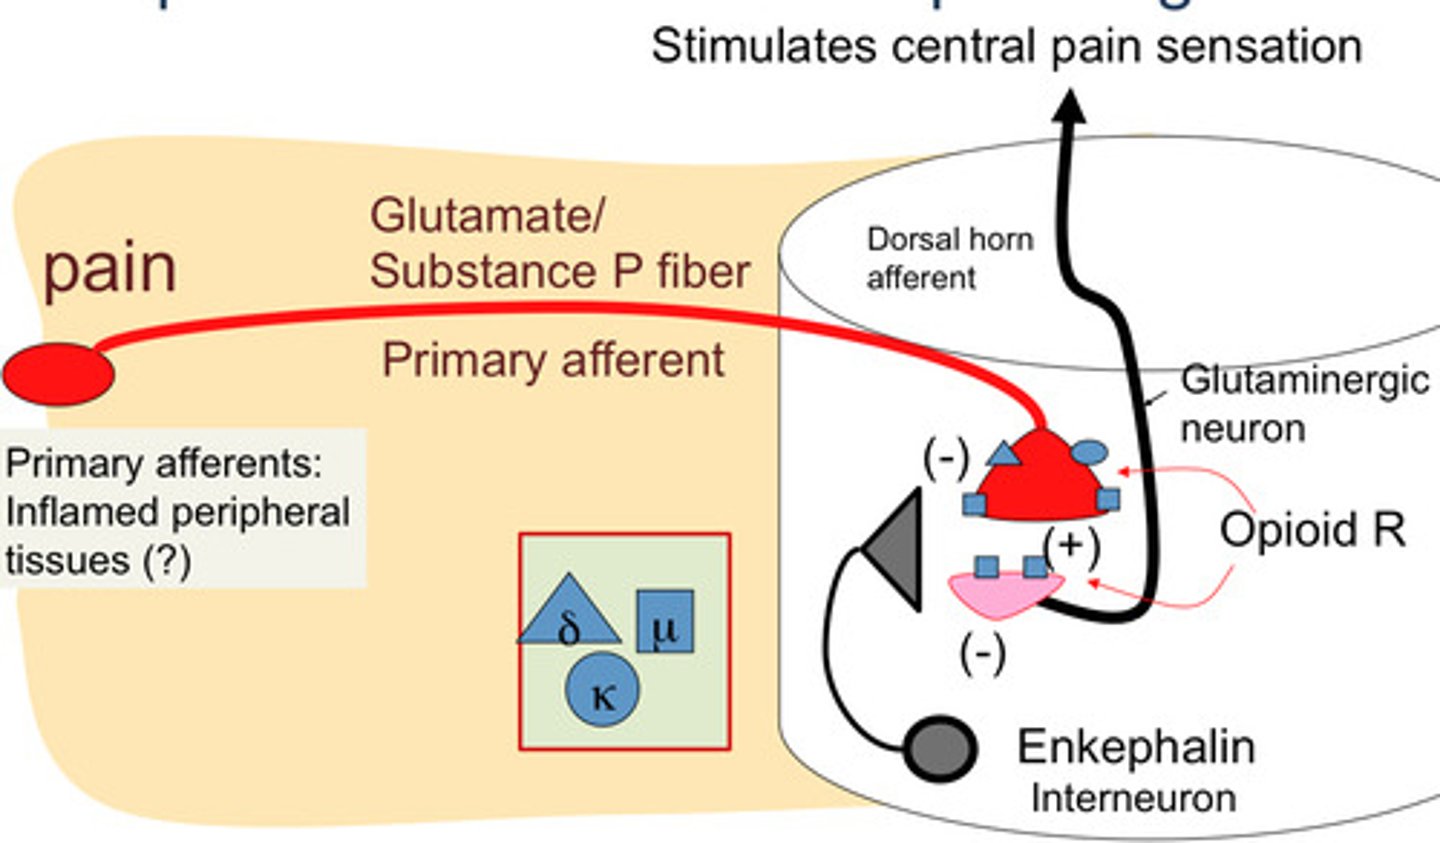

Glutamate

main excitatory neurotransmitter in the nervous system; participates in relay of sensory information and learning

Substance p

a neurotransmitter that is involved in the transmission of pain messages to the brain

Endorphins

natural, opiate-like neurotransmitters that help manage pain, pleasure, stress, mood

Interneurons

neurons that transfer messages to other neurons nearby